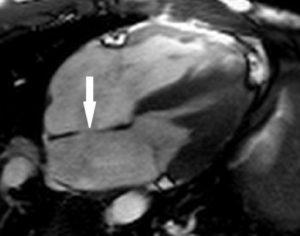

ДМПП. Четырехкамерный срез (ЭХО-КГ) демонстрируетширокий дефект (стрелка) в межпредсердной перегородке (с разрешения L.Sieverdingи G.Greil, Tübingen)

Рисунок 1. МРТ. Четырехкамерное сечение сердца. Стрелкой указан дефект межпредсердной перегородки (ДМПП).